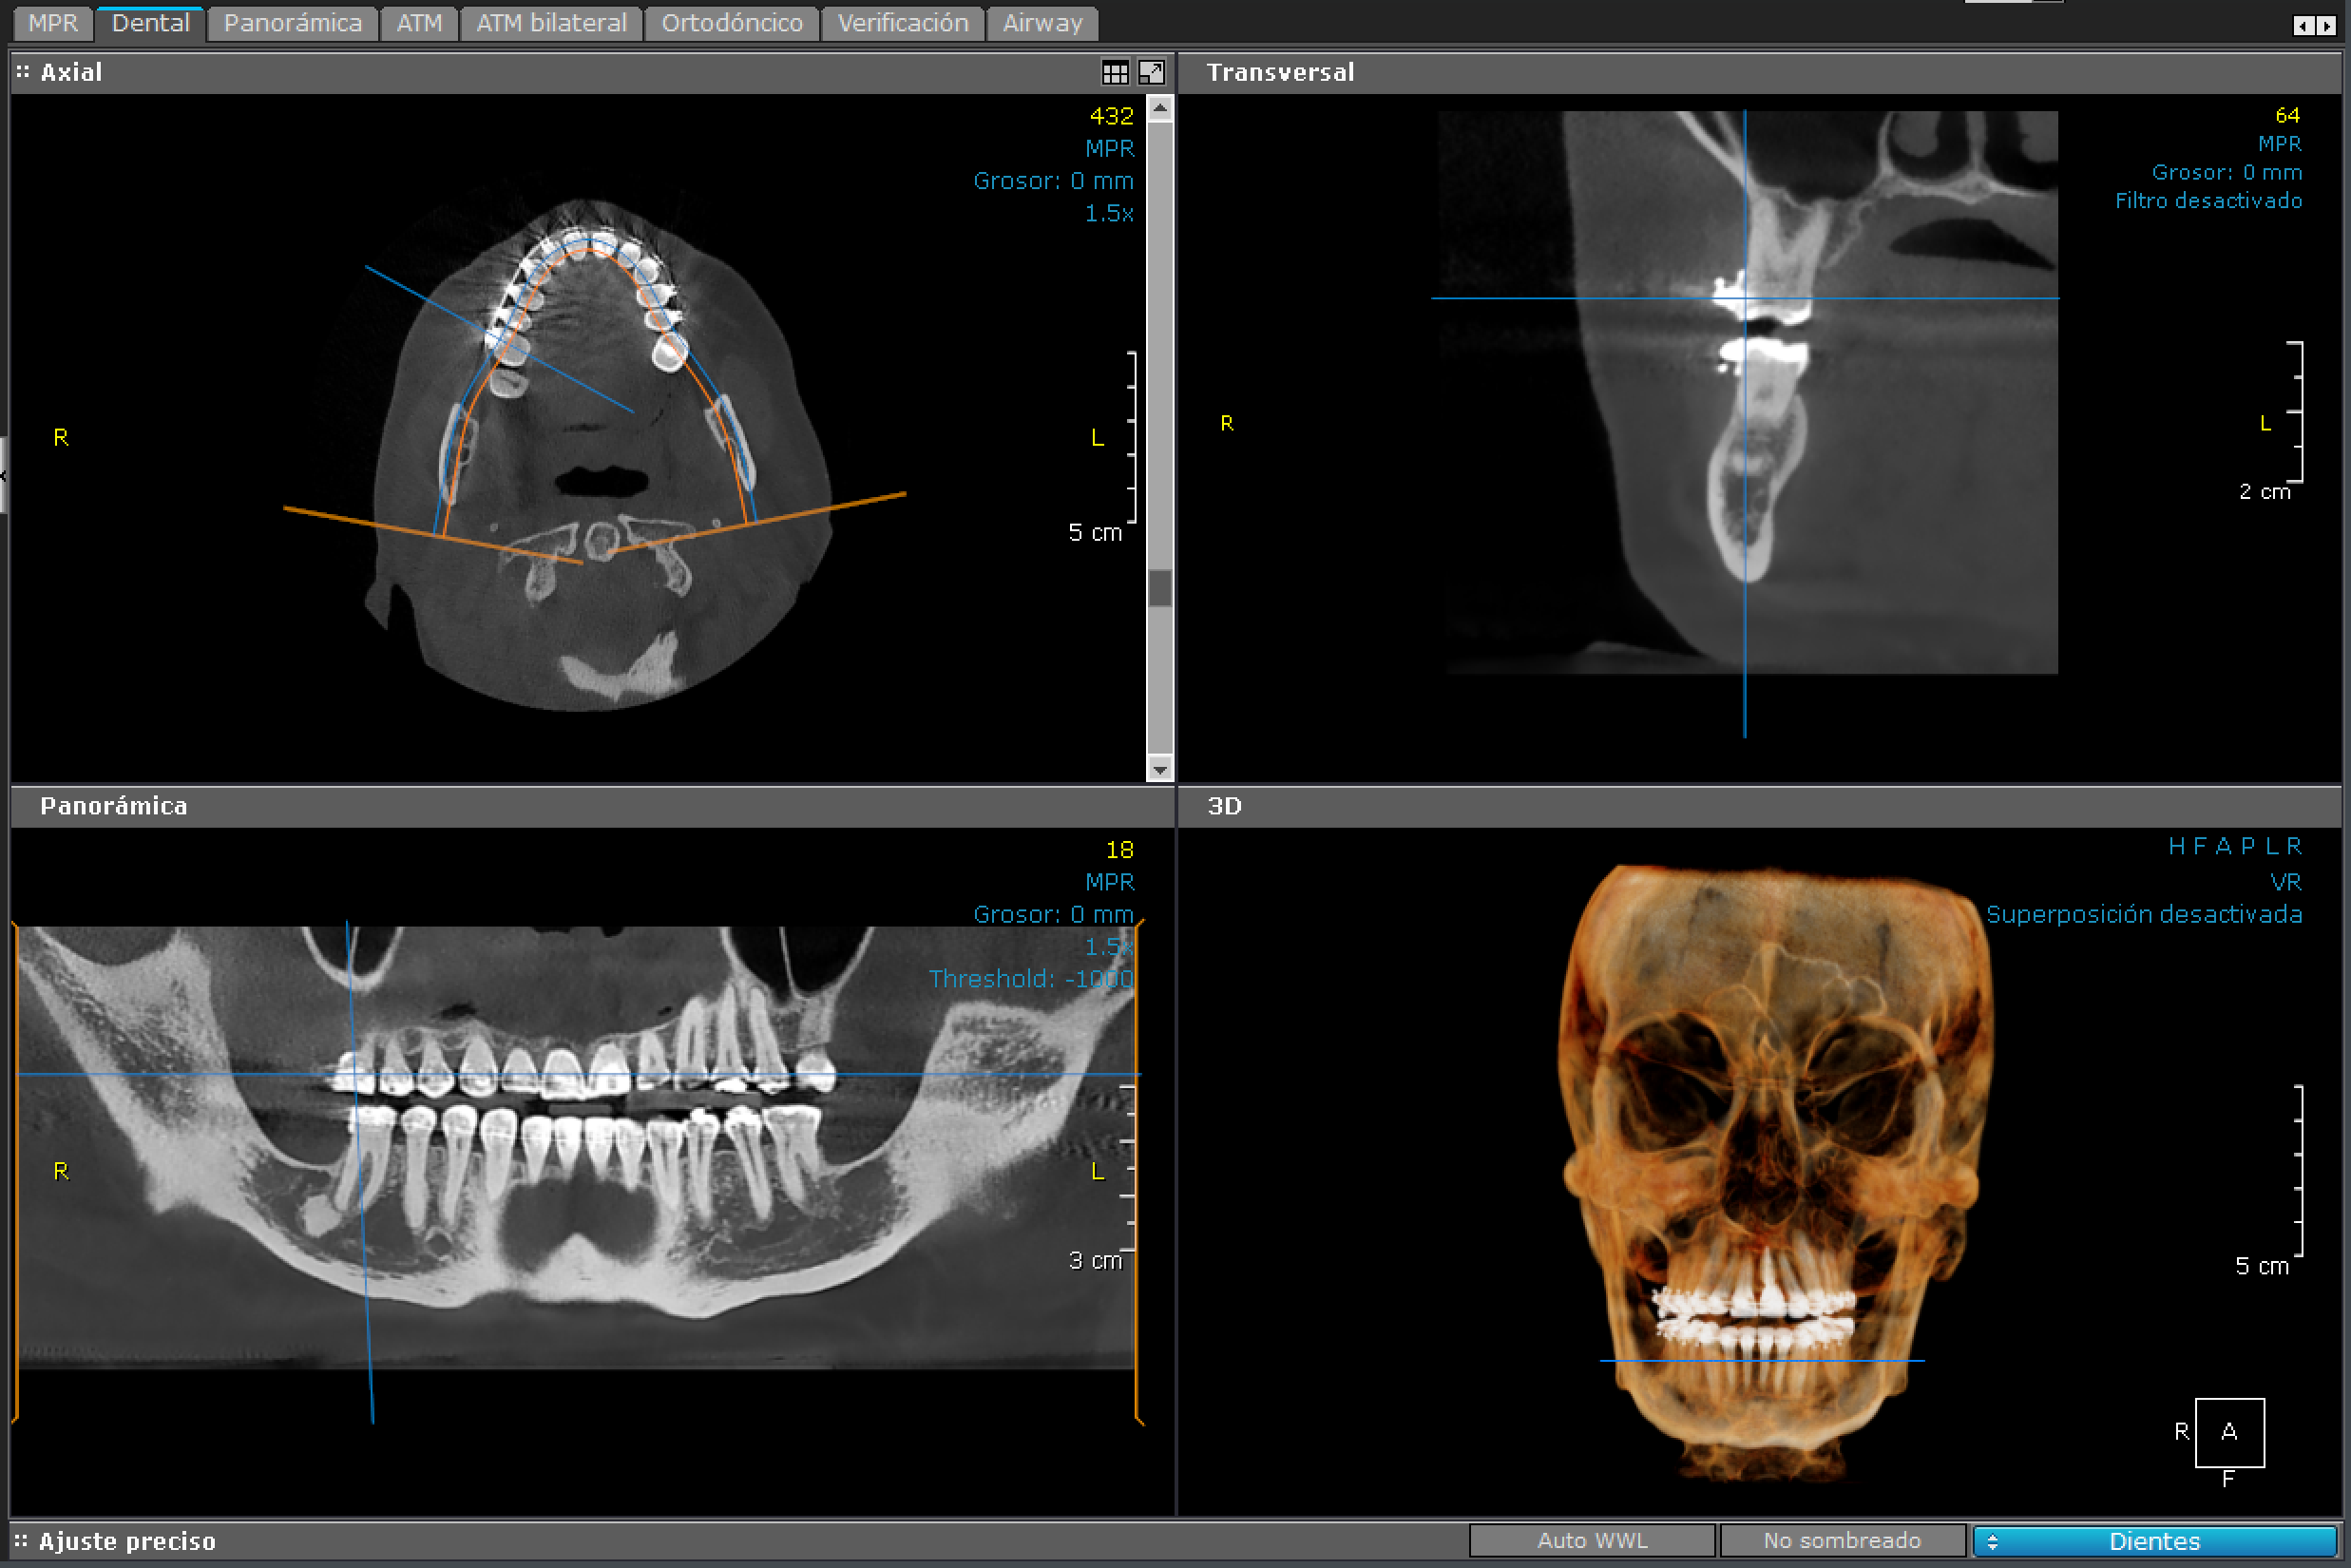

3D - Bimaxilar

bimaxilar

Es un examen radiológico computarizado de ambos maxilares. Es de especial ayuda para la planificación de cirugía dentales.